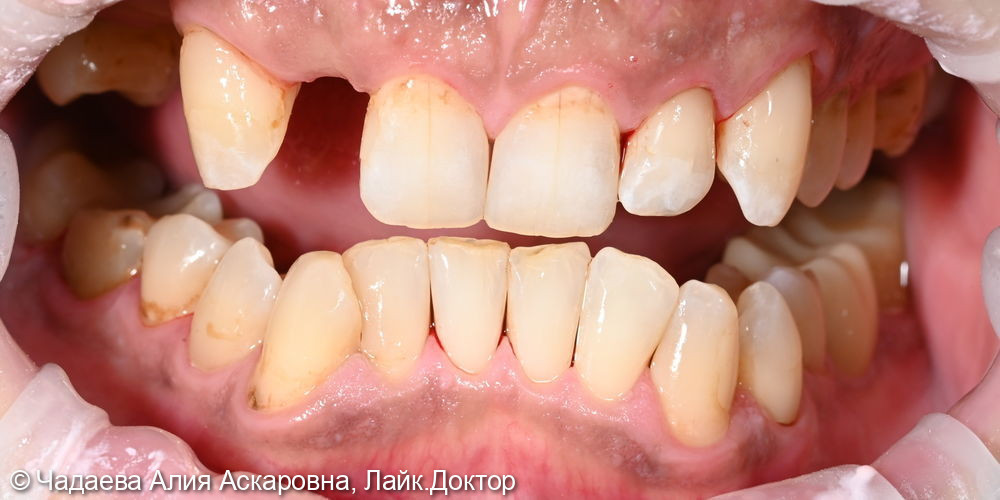

Пациент обратился с жалобами на наличие надесневых зубных отложений и пигментного налета. При проведении осмотра было выявлено наличие надесневых отложений и пигментного налета.

Проведена комплексная профессиональная гигиена полости рта по швейцарскому протоколу GBT. Удаление зубных камней и зубного налета аппаратом Air-flow, полировкаПоказать полностью... зубов, фторирование (покрытие фторлаком).